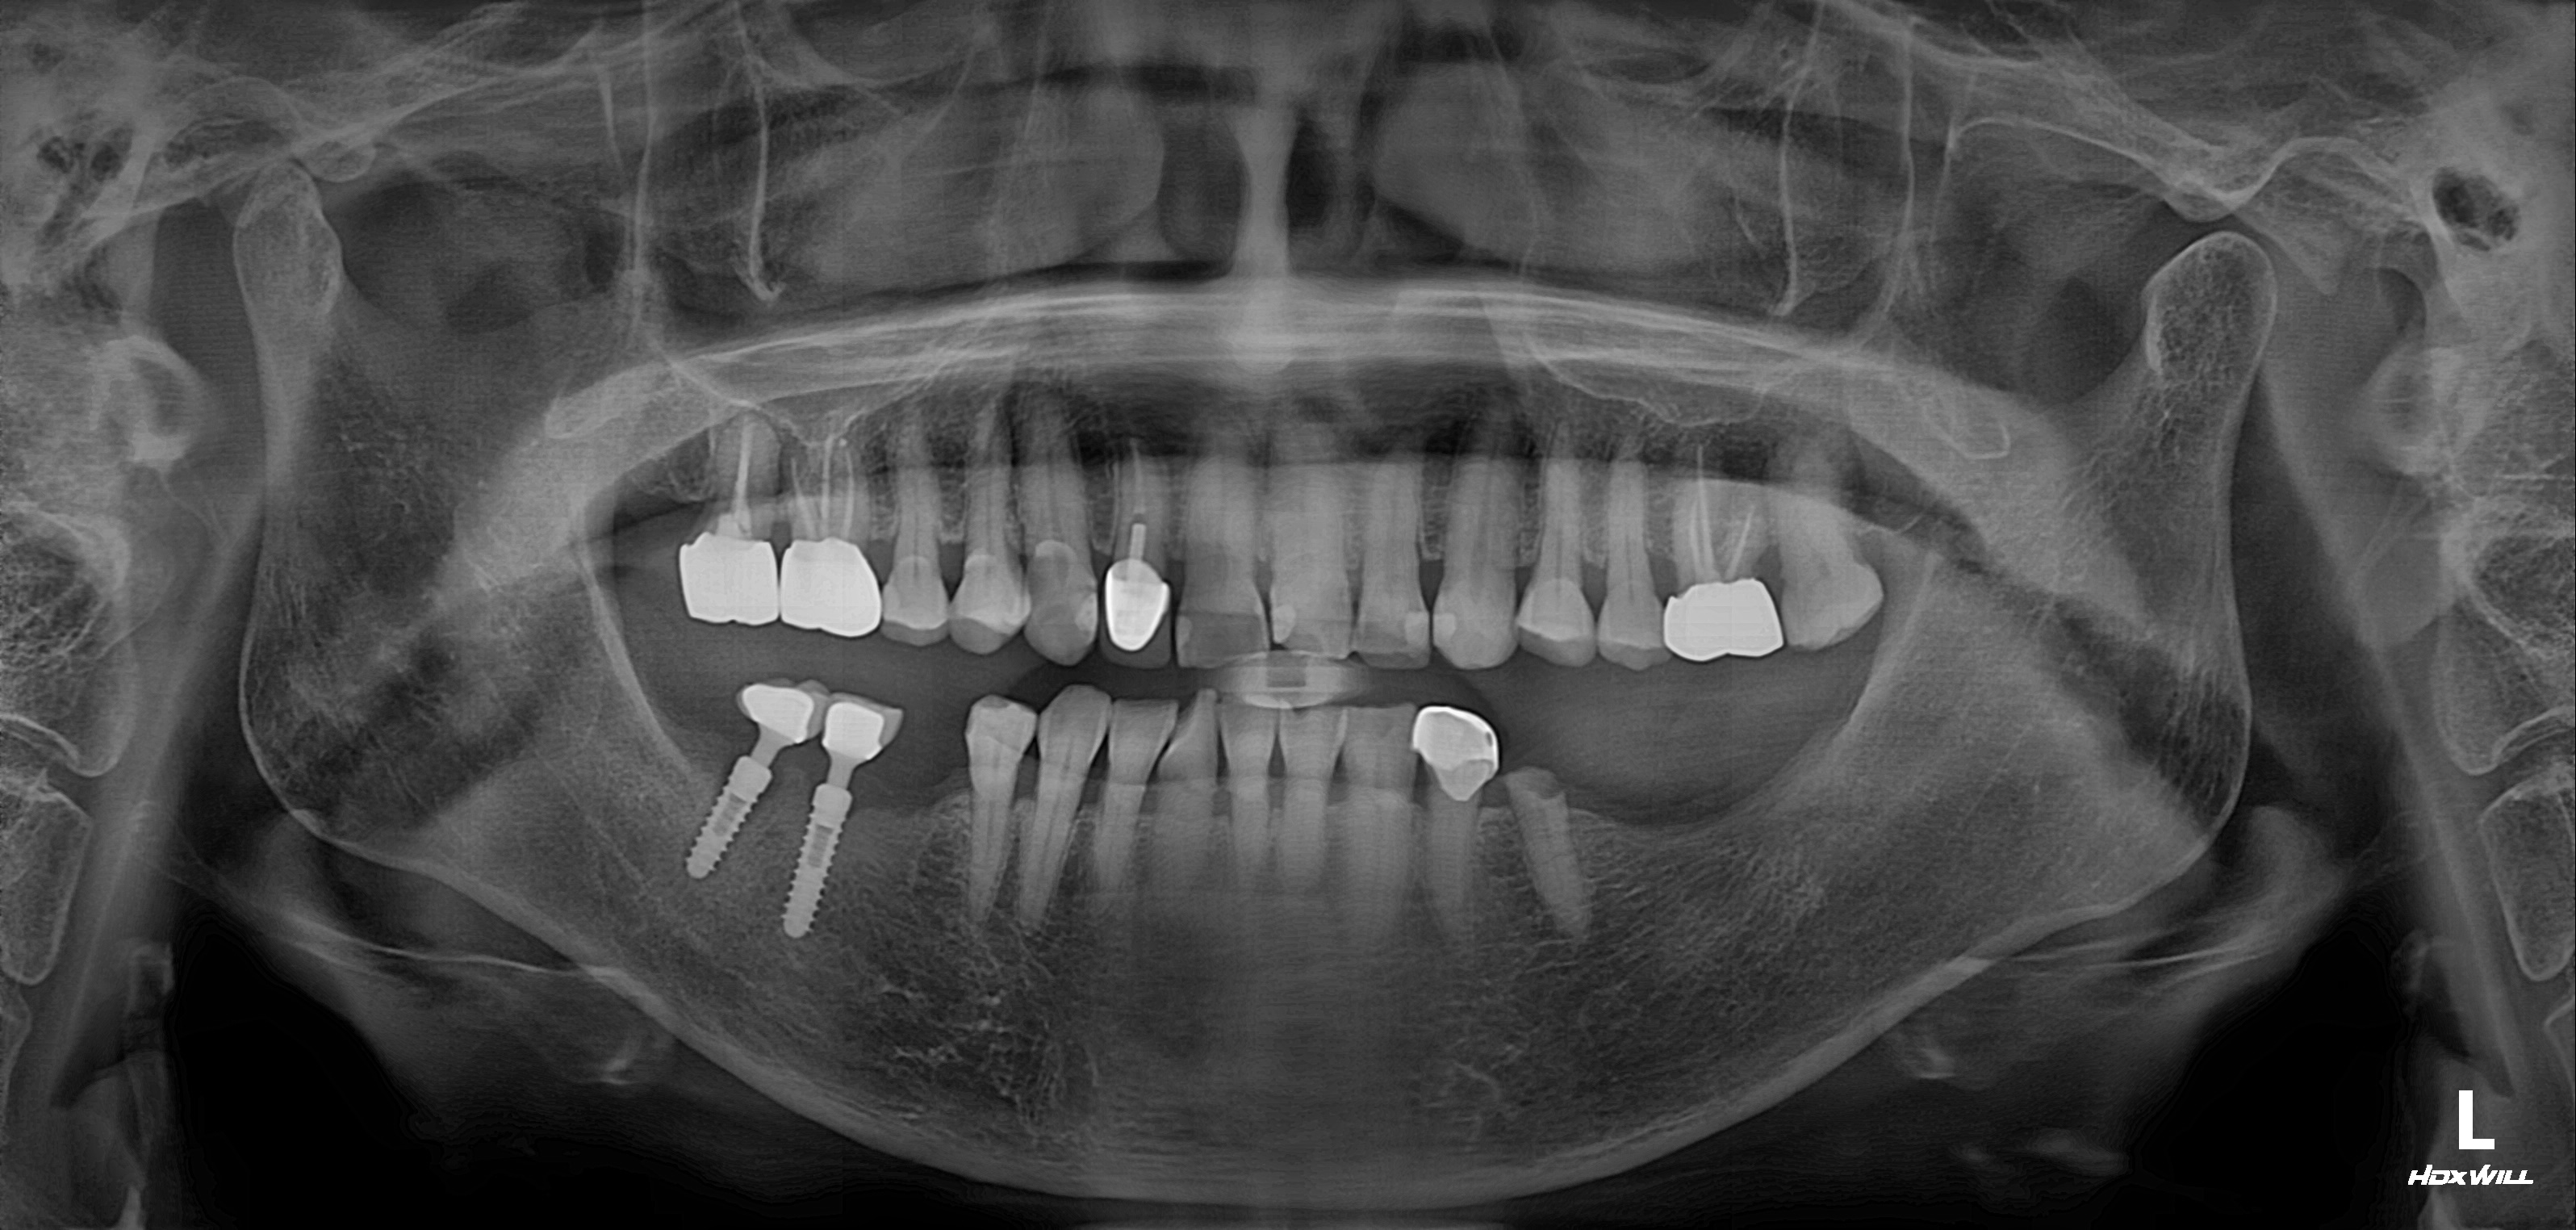

수술 전

수술 후

하악 임플란트 식립사례

전후사진